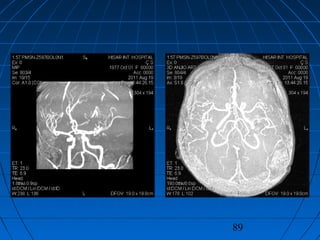

 DÖ: 59 yaşında erkek hastaDÖ: 59 yaşında erkek hasta

 BaşağrısıBaşağrısı (akut şiddetli, son 24 saat(akut şiddetli, son 24 saat

içinde)içinde)

 GKS 14 (WFNS grade 2)GKS 14 (WFNS grade 2)

 Fisher grade IVFisher grade IV

CERRAHİCERRAHİ

 Sol pterional trans-sylvian yaklaşımSol pterional trans-sylvian yaklaşım

 AcomA Anevrizması kliplendiAcomA Anevrizması kliplendi